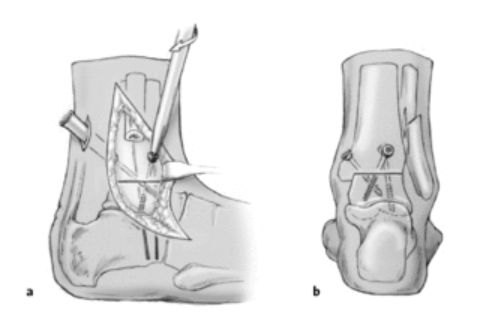

Las fracturas de pierna, pie y tobillo son lesiones frecuentes que pueden producirse por caídas, accidentes deportivos o traumatismos de mayor energía, y requieren una evaluación especializada para evitar secuelas funcionales. Según el tipo de fractura, su localización, el grado de desplazamiento y las características del paciente, el tratamiento varia. Se realiza una evaluación clínica e imagenológica completa para definir la conducta más adecuada en cada caso, que puede incluir manejo conservador con inmovilización o quirurgico de ser el caso. El objetivo es lograr una correcta consolidación ósea, aliviar el dolor y recuperar la función, priorizando una rehabilitación segura y progresiva.